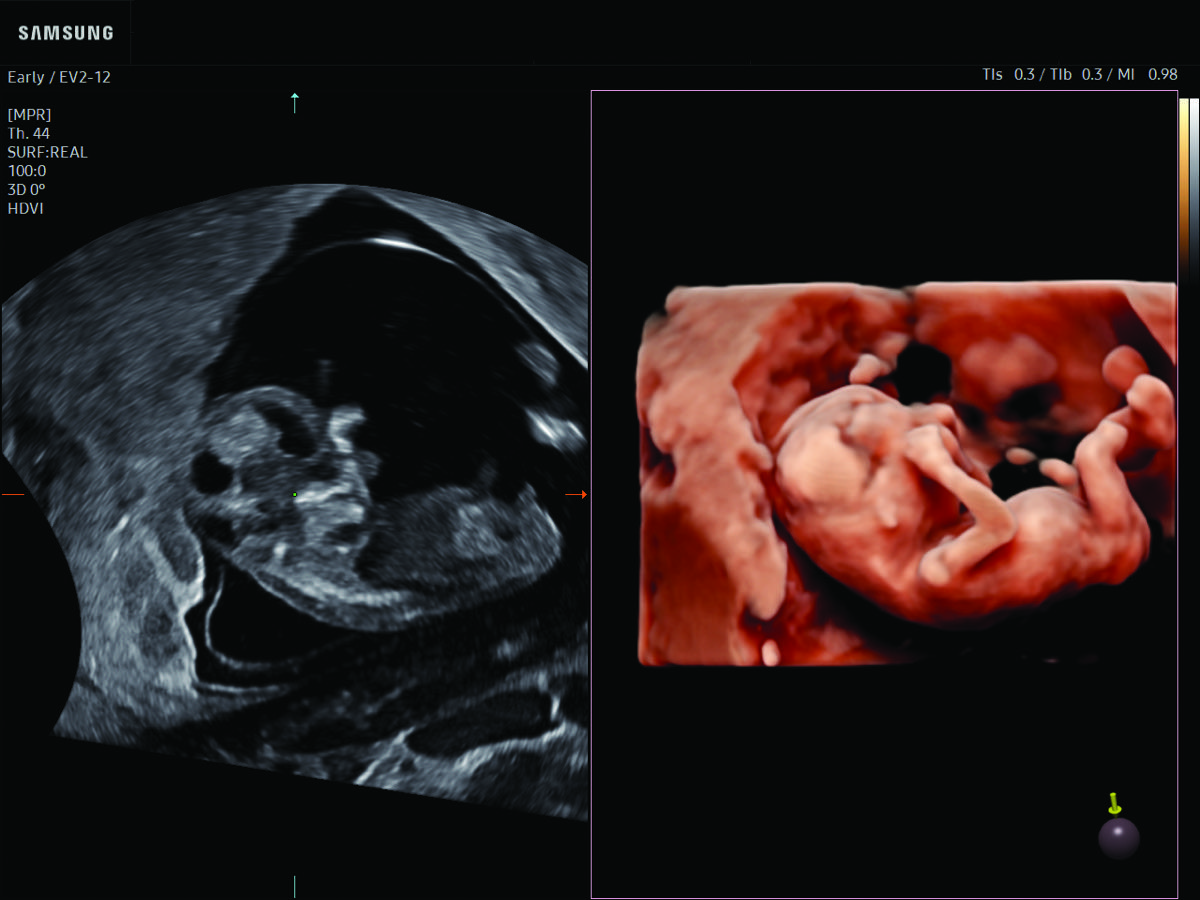

Comprehensive, advanced and expert MFM care for high-risk pregnancies

- Fetal anomalies